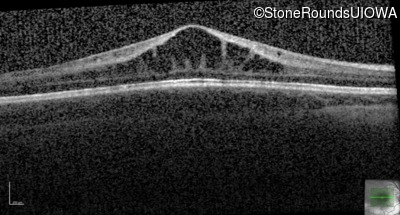

This 6 year old boy first experienced difficulty reading and seeing the blackboard at age 5.

| Age at visit: 14 years |

| Age at visit: 14 years (Visit 2) |